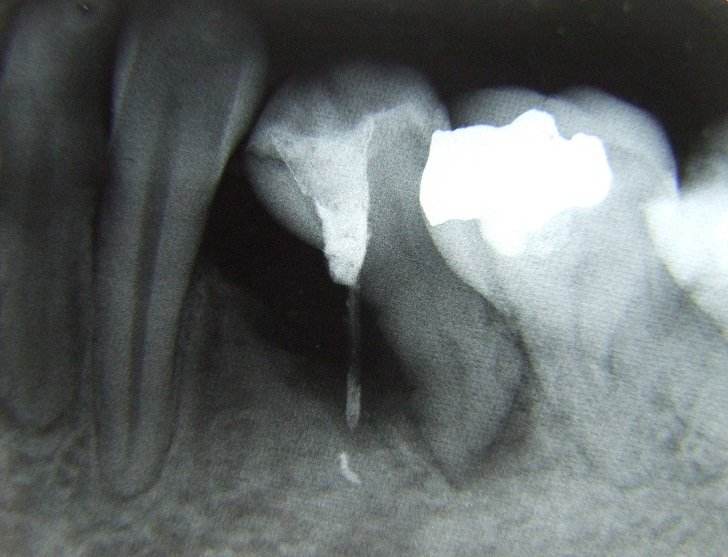

Desi nu este de dorit, uneori se constata prezenta unor leziuni extinse (granuloame, chisturi) care daca nu sunt rezolvate corespunzator, pun in pericol viabilitatatea dintelui.

Din nou tratamentul sub microscop optic efectuat de catre specialistii endodonti poate duce la salvarea dintelui.